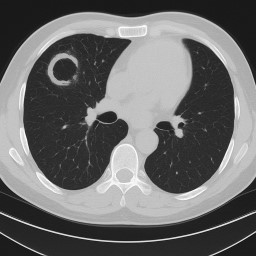

Other forms of aspergillosis: Aspergilloma (Fungal Ball in the Lung)

Aspergilloma (Fungal Ball in the Lung)

An aspergilloma is a clump of fungus (usually Aspergillus) that grows inside an old cavity in the lung. These cavities often form after conditions like tuberculosis (TB), other lung infections, or lung disease. The fungus does not usually invade healthy lung tissue, but it uses the cavity as a space to grow.

How is it found?

-

An aspergilloma usually shows up on a chest scan (X-ray or CT).

It often looks like a round “ball” inside a cavity in the upper part of the lung.

Sometimes it can move around a little inside the space.

Important note: Aspergillomas are not cancer, but they can sometimes be mistaken for cancer on scans. For this reason, doctors may arrange extra tests (such as blood tests, repeat scans, or sometimes biopsy) and may refer patients to the National Aspergillosis Centre (NAC) to be certain of the diagnosis.